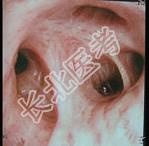

- 单项选择题67岁男性,吸烟史30余年, 反复咳嗽咳痰20年,支气管镜见气管壁粘膜明显纤维化, 可能的诊断是 ( )

A、慢性支气管炎

B、急性支气管炎

C、肺间质病

D、支气管内膜结核

E、支气管扩张